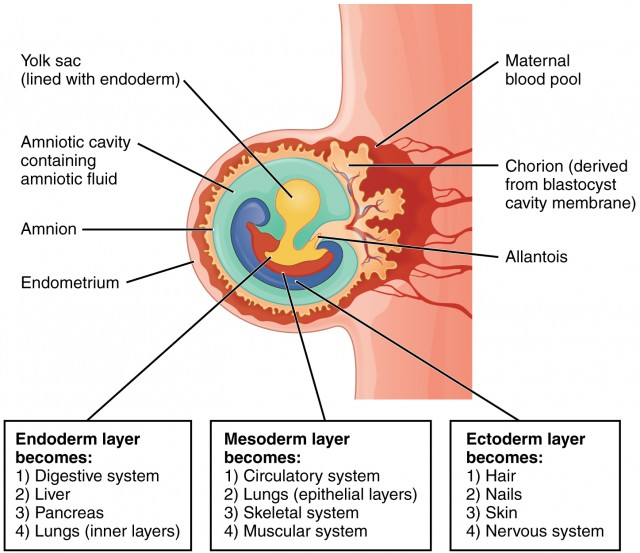

Primary Germ Layers

At the time of implantation, a blastocyst already has differentiated to a point at which two separate cavities appear in the inner structure: (1) a large one, the amniotic cavity, which is lined with a distinctive layer of cells, the ectoderm, and (2) a smaller cavity, the yolk sac, which is lined with entoderm cells. In humans, the yolk sac appears to supply nourishment only until implantation. After that, its main purpose is to provide a source of red blood cells until the embryo’s hematopoietic system is mature enough to perform this function (at about the 12th week of intrauterine life). The yolk sac then atrophies and remains only as a thin white streak discernible in the cord at birth. Between the amniotic cavity and the yolk sac, a third layer of primary cells, the mesoderm, forms. The embryo will begin to develop at the point where the three cell layers (ectoderm, entoderm, and mesoderm) meet, called the embryonic shield. Each of these germ layers of primary tissue.

Knowing the origins of body structures helps to explain why certain screening procedures are ordered for newborns with congenital malformations. A radiographic examination of the kidney, for example, may be ordered for a child born with a heart defect. A child with a malformation of the urinary tract is often investigated for reproductive abnormalities as well.

All organ systems are complete, at least in a rudimentary form, at 8 weeks gestation (the end of the embryonic period). During this early time of organogenesis (organ formation), the growing structure is most vulnerable to invasion by teratogens (any factor that adversely affects the fertilized ovum, embryo, or fetus, such as cigarette smoking).